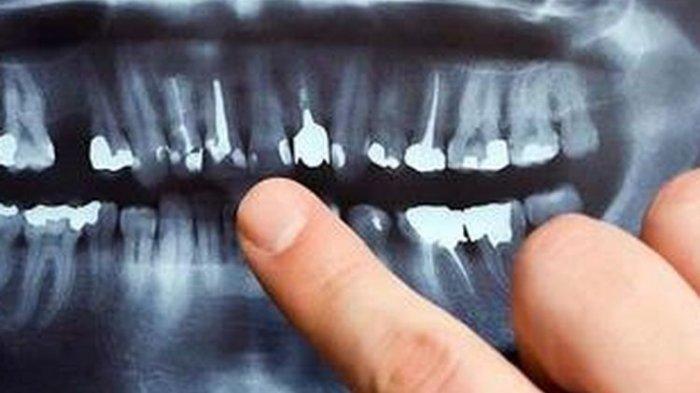

TRIBUNHEALTH.COM - Impaksi pada gigi merupakan kondisi gigi terpendam atau terjebak didalam gusi.

Impaksi gigi adalah gigi yang tumbuhnya sebagian, atau gigi yang bererupsi hanya sebagian.

Terbanyak kasus pada gigi geraham ketiga, gigi taring, dan gigi premolar kedua.

Penyebab impaksi adalah dimensi rahang yang tidak mencukupi untuk tumbuhnya gigi yang normal.

Secara radilogi maupun pemeriksaan klinis, hasil prognosanya buruk karena tidak bisa tumbuh sebaiknya dilakukan pengambilan.